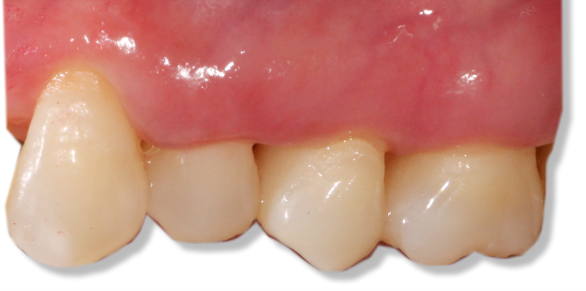

Before and after Periodontal Therapy

![]() | ![]() |

| Untreated severe gum disease | Gum disease treated and stabilised by Dr Halai |